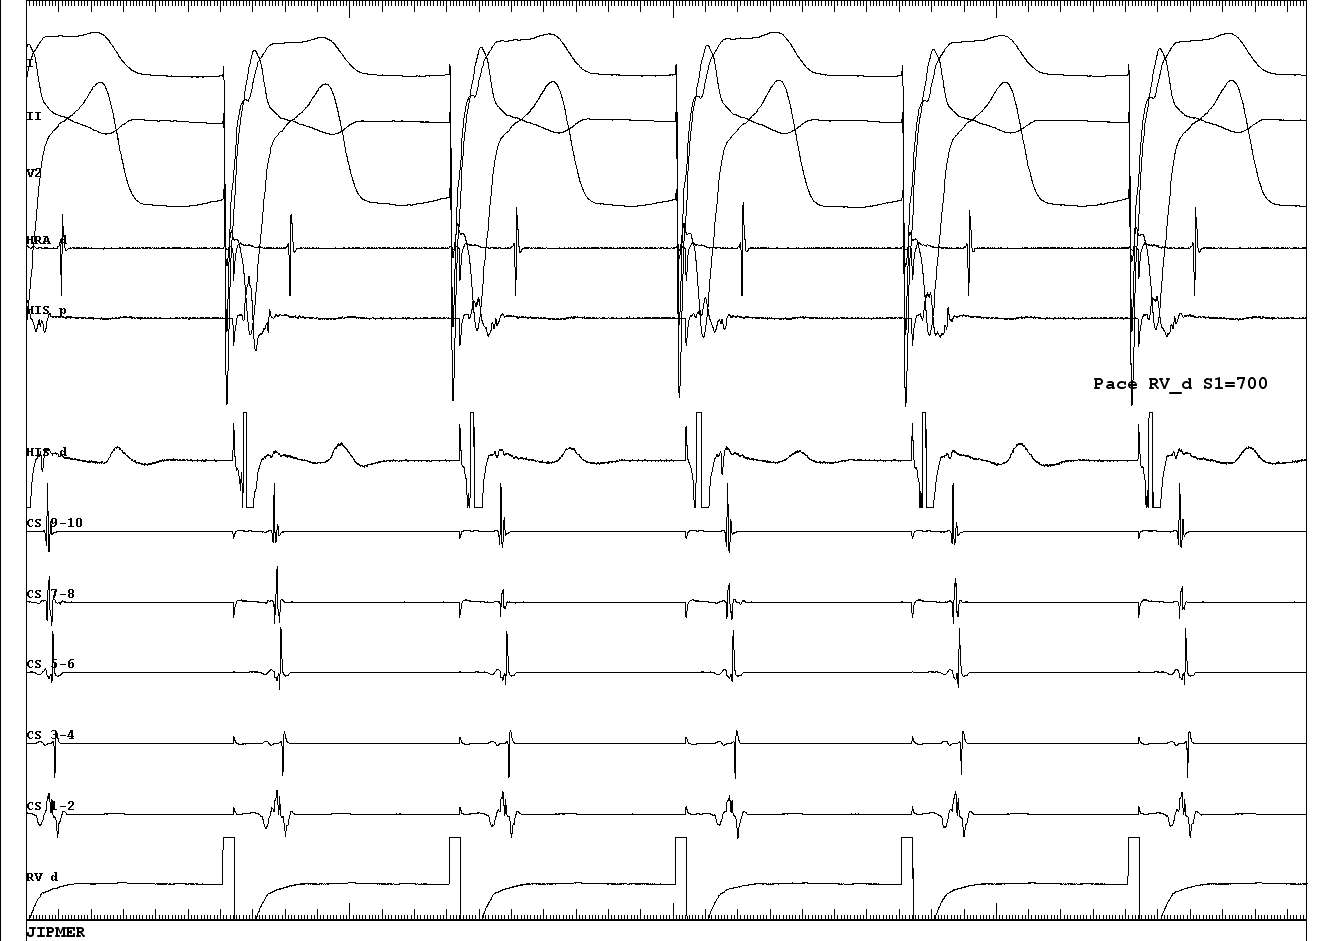

Ventricular overdrive pacing

05_VOP.JPG